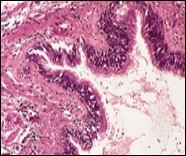

Cystic structures cogitated within deep dermal or subcutaneous tissue can be impacted with haemorrhagic fluid. Cyst lining is smooth, regular and is essentially composed of a singular layer of columnar epithelium with focally pseudostratified columnar epithelium, a circumscription of loosely configured, well vascularized, fibroconnective or fibrocollagenous tissue and an absence of inflammatory infiltrate.

Figure 2.Ciliated cutaneous cyst with an undulating layer of ciliated cuboidal epithelium and supporting fibrous tissue framework (12).

Figure 3.Ciliated cutaneous cyst with a coating of plump, ciliated columnar epithelium and a circumscribing fibro - connective tissue (12).